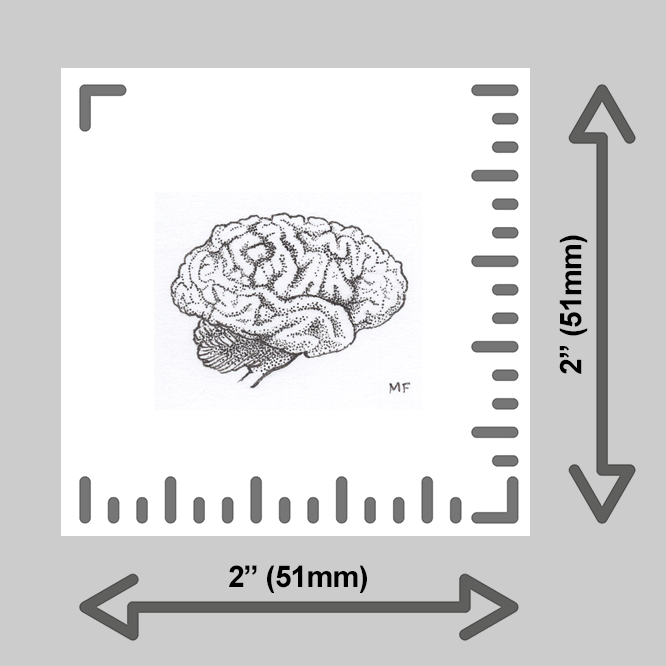

learn more about these prints below:

Each tiny print is made by hand by yours truly in my Michigan studio using an EPSON P600 printer. Only the finest heavy matte archival, museum-quality, paper is used; color and finish are inspected thoroughly for each print before framing and shipping.

Want to upgrade your print? Add a wee frame! You have four options for framing your tiny print:

A sturdy 2×2” wood frame with a saw tooth hanger, or,

A 2×2” clear acrylic magnet frame, or,